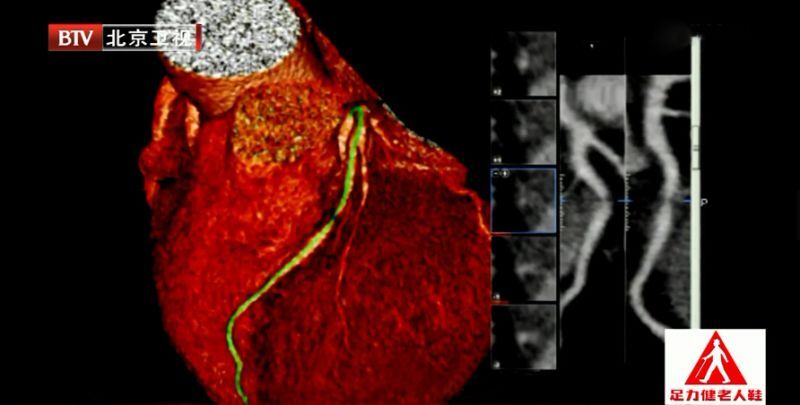

临床上,如果医生觉得这个患者需要做影像学检查来明确血管是否有病变的,在医院门诊可以做一个冠状动脉CT检查(加强CT)。冠状动脉CT检查需要打含碘的造影剂,红色血管在打完造影剂后就会显影,拍出胶片就能看到血管。

【专家提示】超声看不到细小的血脂,只有冠状动脉CT检查可以看得最清楚。这项检查要吃放射线,而且打的含碘的造影剂可能有过敏反应,需不需要做这项检查医生会为您评估,请遵医嘱。